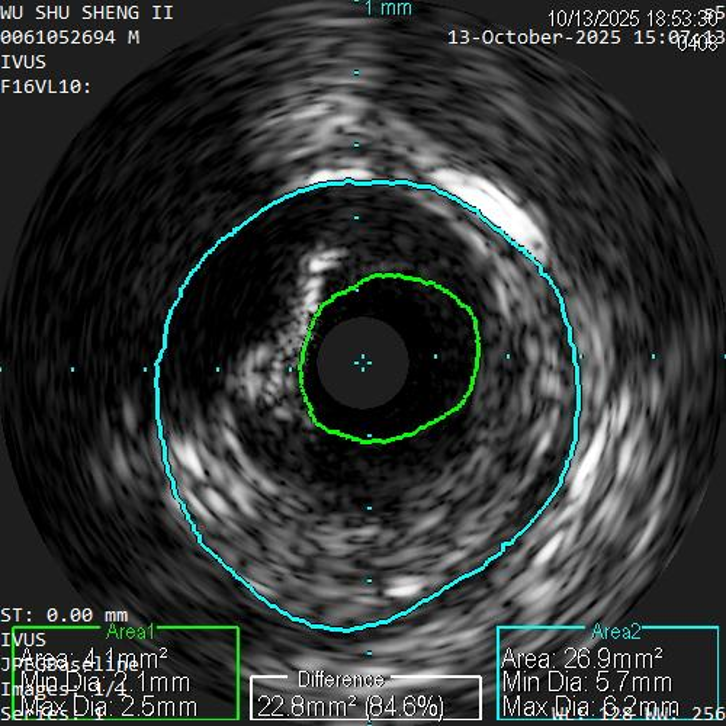

股浅动脉中远段及腘动脉重度狭窄、环周钙化明显

IVUS提示病变段仍有局部重度狭窄,遂选择最新上市的”始祖鸟”紫杉醇药物涂层球囊(5*150mm、6*150mm )对残余狭窄进行扩张

IVUS提示病变段仍有局部重度狭窄,遂选择最新上市的”始祖鸟”紫杉醇药物涂层球囊(6*150mm、 5*150mm ) 分别对股浅动脉、腘动脉、胫腓干动脉逐段扩张,压力至工作压维持3分钟。